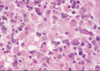

Name, characteristics, ring enhancing?

Glioblastoma multiforme

Pseudopallisading necrosis and microvascular proliferation

Ring enhancing - due to breakdown of BBB